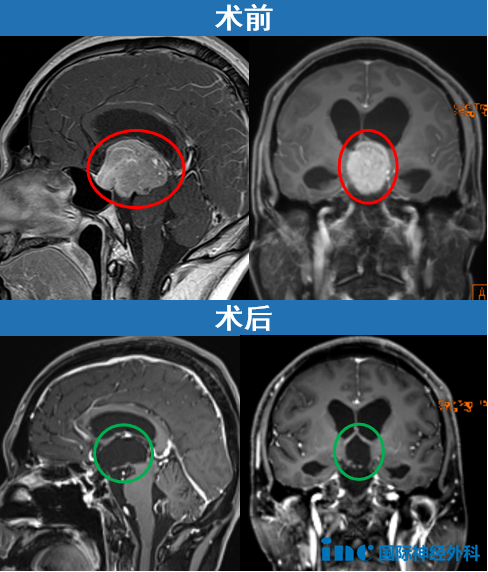

一位62岁女性患者,与垂体瘤抗争长达35年,曾因垂体瘤复发接受放射治疗。此次因出现复视症状随访,发现已经发展巨大的垂体瘤。

进行开颅手术,术后影像片子显示肿瘤切除干净。